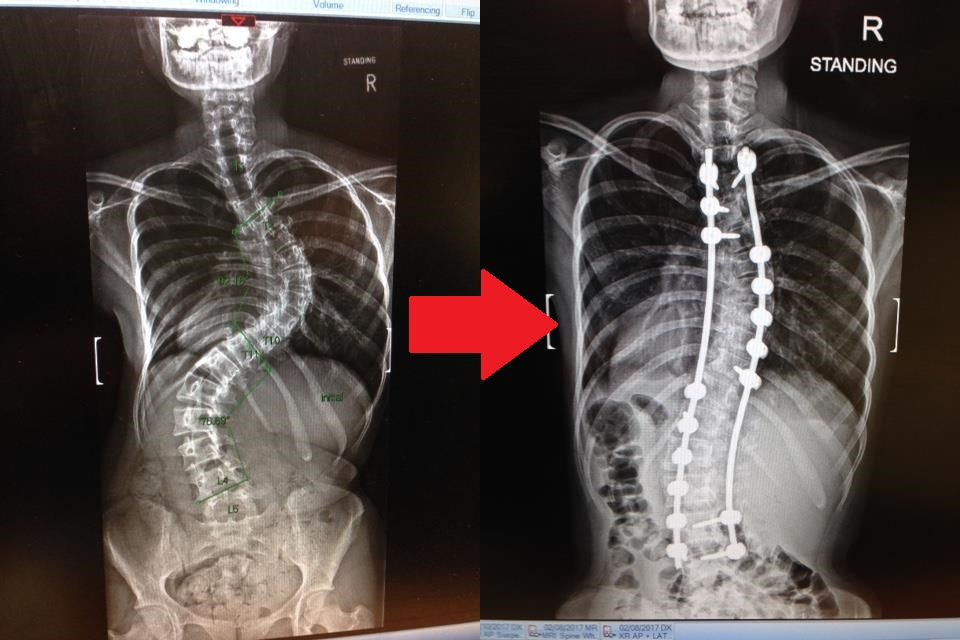

「さあ、ご家族の皆さん!

用意はいいですか?

いよいよ撮影会ですよ!」

と

待ちに待ったレントゲン写真を

陽気にお披露目してくれた。

↓

感無量(号泣

ドクター

ありがとうございました(合掌